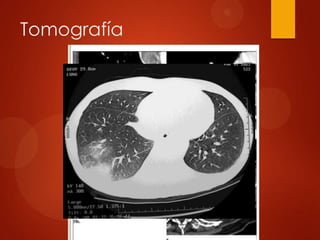

Tomografía